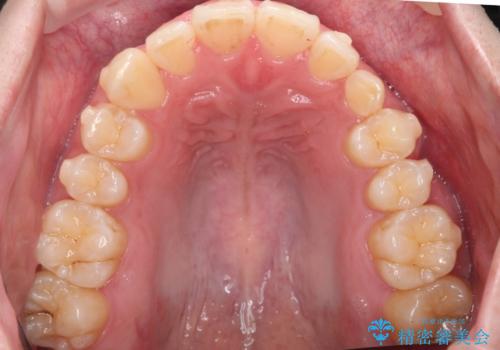

左上の乳犬歯が残っており、その下から生えてくるはずの犬歯(永久歯)が左上小臼歯部に萌出していました。

左上の乳犬歯は根もしっかりしていたため、

➀そのまま矯正する。乳歯がいずれダメになったときにそこはブリッジかインプラントを検討する

②乳歯は抜歯し、ブリッジかインプラントを矯正後に入れる

を提案し、➀を選択されました。

将来的にインプラントは希望されないとのことだったため、乳歯の部分は隙間を開けてインプラントを入れる用のすき間を確保するということは特に行いませんでした。

乳歯をそのまま並べたため、上顎の左右の犬歯の幅は非対称になっています。